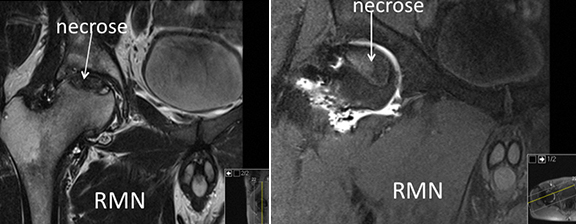

O que causa a osteonecrose é a falta de aporte sanguíneo geralmente á região anterosuperior (área de suporte de carga) da cabeça do fémur o que leva à necrose (morte) do osso dessa zona.

O trauma é uma causa comum de osteonecrose e acontece porque há lesão das artérias nutritivas da cabeça do fémur (fracturas da cabeça ou do colo do fémur, luxação da anca).

Algumas condições atraumáticas (doença de Caisson, doença de células falciformes, doenças mieloproliferativas, doenças da coagulação) podem causar osteonecrose pelo deficit de irrigação sanguínea do osso.

A maioria dos casos de osteonecrose são de causa desconhecida, mas têm numerosos factores de risco associados (uso de corticoesteroides, alcoolismo, tabagismo, lupus, doença renal crónica, doença inflamatória da bexiga, infecção pelo HIV, hipertensão, transplantados, hiperlipidemia, gravidez, quimioterapia), e alguns indivíduos têm predisposição genética para osteonecrose.

Com o tratamento médico nos estádios pré-colapso pretende-se melhorar a função e aliviar a dor, prevenir a progressão para colapso e promover a cura da lesão de necrose.

O enxerto ósseo vascularizado proporciona um suporte estruturado viável (perónio vascularizado, enxerto vascularizado da crista ilíaca) para prevenir o colapso da cartilagem.

Por causa da irrigação sanguínea e potencial poder osteogénico, o enxerto vascularizado leva à recuperação da área de osso necrótico.

Os resultados são menos bem sucedidos se as lesões necróticas forem de tamanho superior a 50% da cabeça femoral ou se houver um colapso da cartilagem de mais de 2 mm.

A osteotomia intertrocantérica rotacional é feita de forma a colocar a região necrótica da cabeça femoral fora da área de suporte de carga.